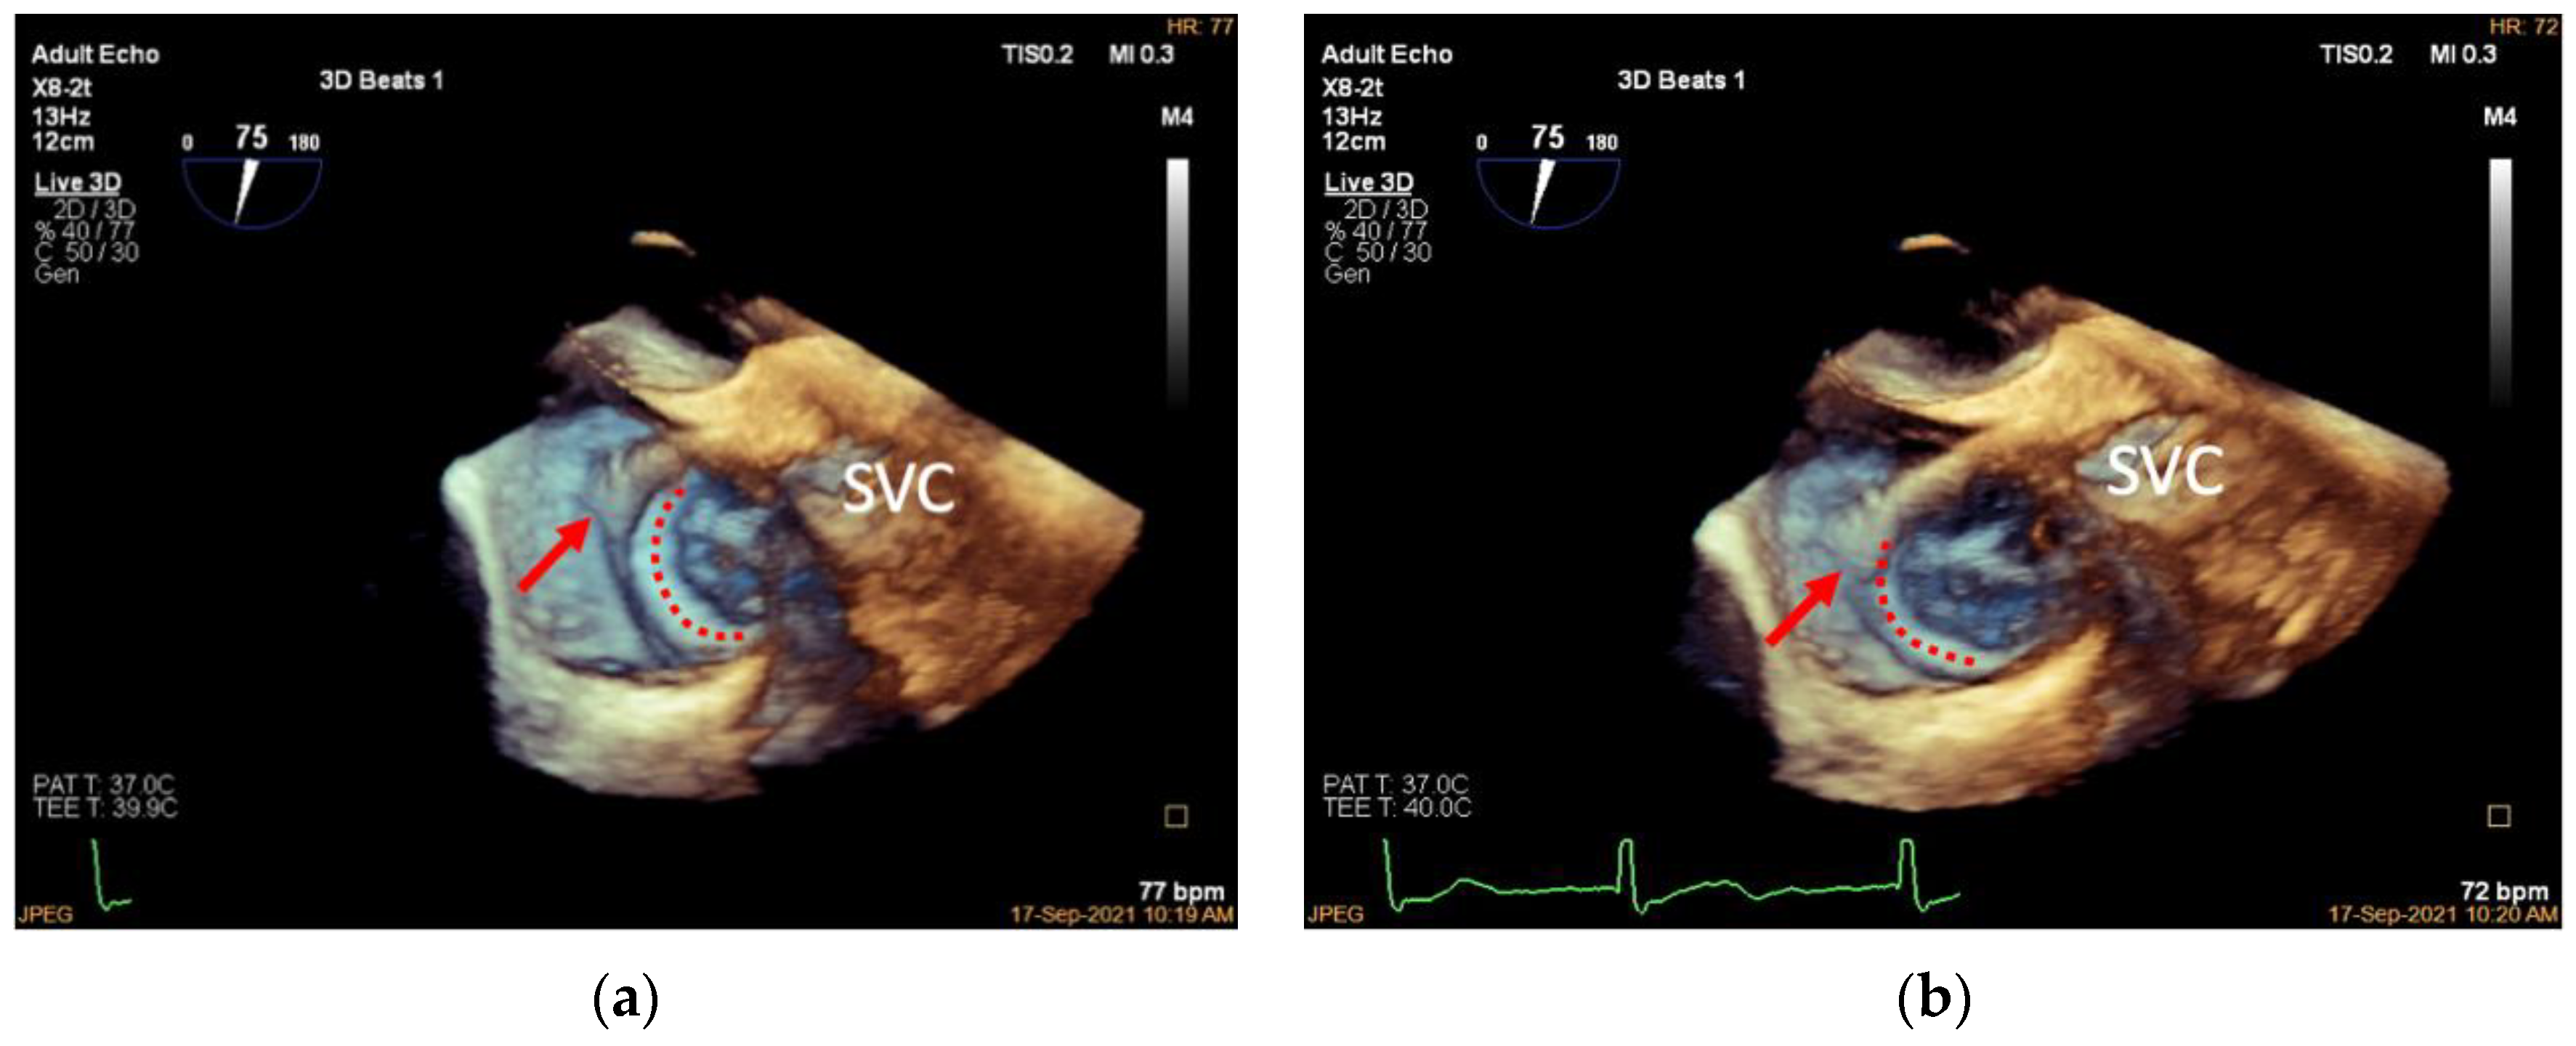

3.4. Adjustment of the Clip Arm and Clamping of Annular Tissue

| Step 3. Adjustment of the clip arm and clamping of annular tissue | 3D TV en face view | about 60° | |